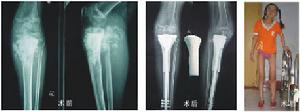

3.骨肉瘤的保肢治療

(1)手術方案的確立決定於對病人的各種資料的評估:①可通過X線片、CT、MRI、X線胸片和骨掃描及DSA進行外科分期和血運情況的估價。②通過新輔助化療前後各種檢查資料的比較,評估腫瘤的生物學行為和化療能否控制的情況。③若病人要求保肢,還應評估腫瘤能否安全地進行廣泛性局部切除,各種重建與軟組織修復如皮瓣移植等。

(2)重建材料的選擇:重建材料的選擇依醫生的經驗、習慣和客觀條件決定,如年輕病人瘤骨殼較完整且有一定強度者,可採用滅活再植瘤骨殼和骨水泥填充加固;也可選用低溫骨庫保存的異體骨進行移植,但應向病人交代容易出現異體骨反應而使保肢失敗;年長者可選用人工關節置換。

(5)股骨中下段巨大腫瘤:可保留神經血管對腫瘤行階段性截除,將小腿鏇轉180°上移再植,用小腿代替大腿,踝關節代替膝關節。用前足穿戴小腿假肢負重走路,而且有一定活動度的膝關節功能。

(6)膝部腫瘤的軟組織修復:腓腸肌肌皮瓣、背闊肌游離皮瓣的移植能使我們有可能將先前可能施行截肢的病人進行肢體搶救手術,特別是脛骨近端的大的病變。